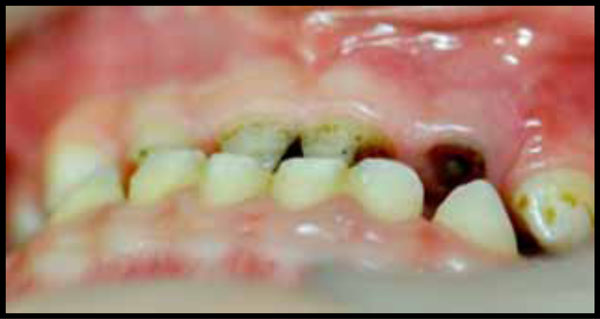

IM, severe ECC before treatment. Note the functional Class III occlusion.

Fig. (13).